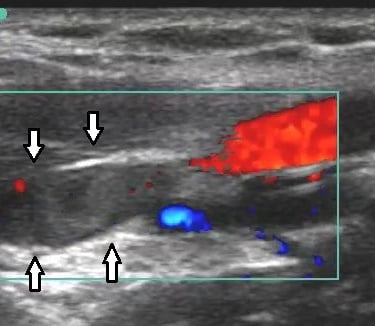

The scan combines two types of ultrasound. One creates clear images of your veins and arteries, while the other (Doppler) shows the speed and direction of blood flow. Together, this provides detailed, real-time information that allows your consultant to make an accurate diagnosis and plan the most appropriate treatment.

Varicose veins are often caused by faulty valves within the veins, leading to blood flowing in the wrong direction (known as venous reflux). These underlying problems cannot always be seen by looking at the veins on the surface of the skin alone.

Duplex scanning allows your consultant to see exactly which veins are affected, where the reflux is coming from, and how severe it is. This information is essential for choosing the most effective treatment and avoiding unnecessary or ineffective procedures.